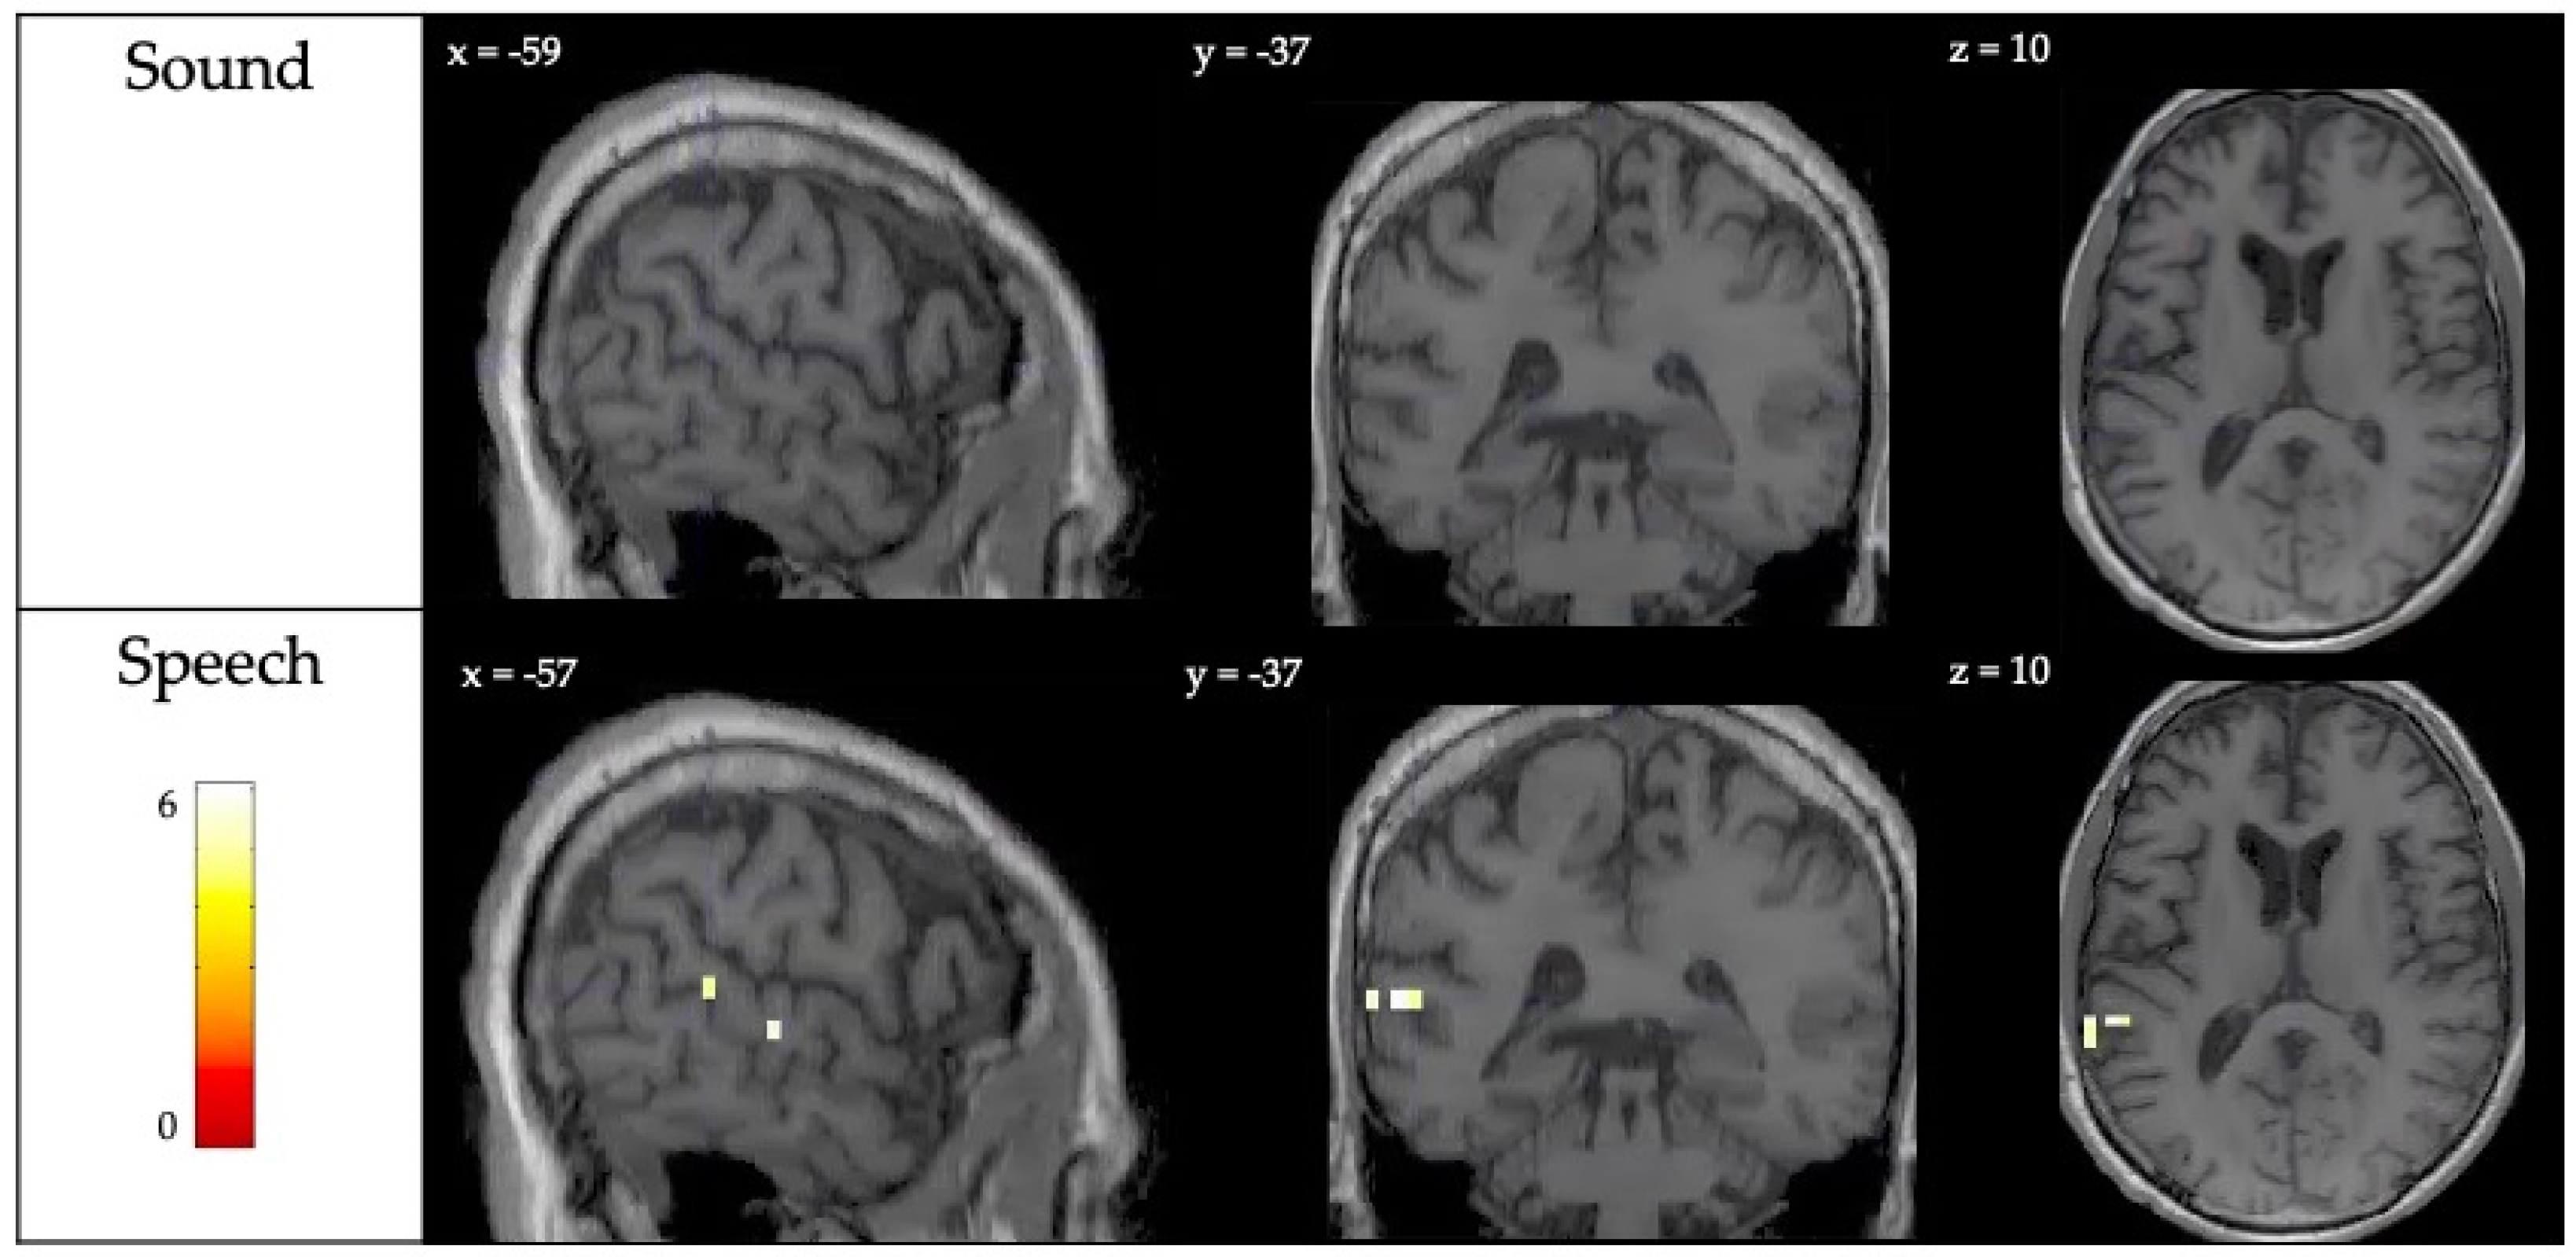

| Speech Perception | Left superior temporal gyrus | −59, −37, 10 | 2 | 5.96 |

| Left superior temporal gyrus | −67, −37, 10 | 3 | 5.37 | |